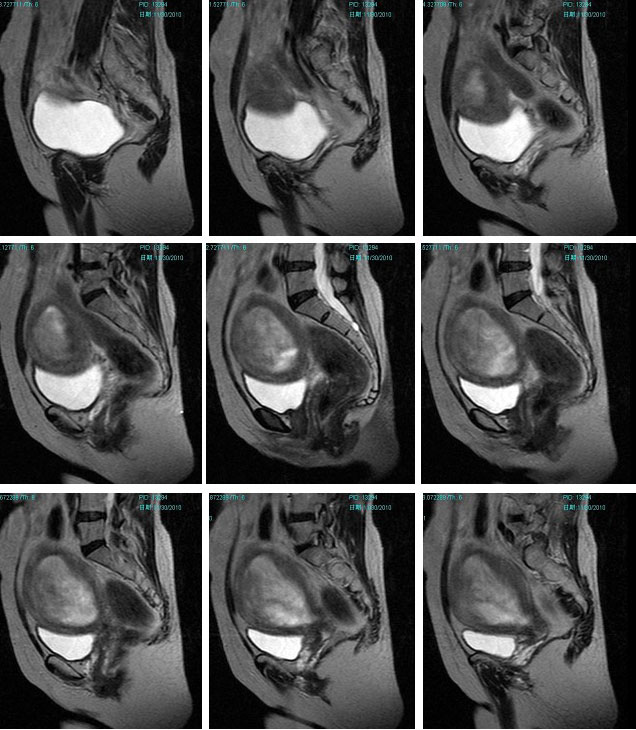

子宫恶性中胚叶混合瘤(癌肉瘤)

女性患者,52岁,月经量大,间断下腹痛一年余。多考虑:1:子宫前壁肌瘤。2:子宫内膜癌可能性大。已取活检,病理结果过几天出来。各位高手先讨论讨论。

子宫内膜太厚,结合带不完整,考虑内膜癌,建议刮宫病检。

宫内膜太厚,结合带不完整,考虑内膜癌,建议刮宫病检。

子宫内膜太厚,结合带不完整,考虑内膜癌,建议刮宫病检。支持!